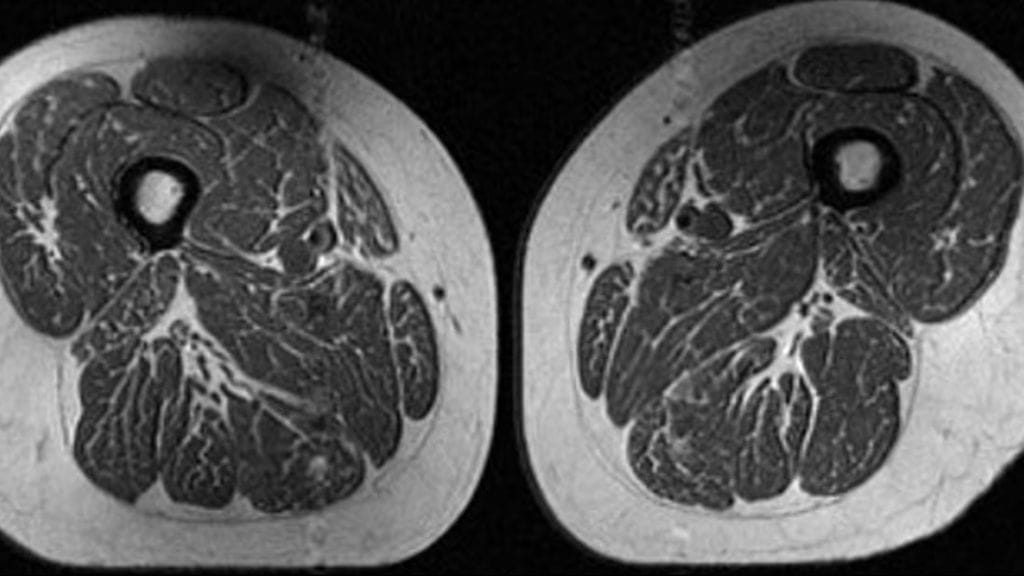

Tutkijat tarkastelivat magneettikuvia ihmisiltä, joilla oli riski sairastua polven nivelrikkoon.

Tutkimusryhmän julkaisema magneettikuva 62-vuotiaan naisen reidestä näyttää voimakkaasti "marmoroituneelta" samalla tavalla kuin vaikkapa entrecôt-pihvi.

Tutkijoiden mukaan nainen sai 87 prosenttia vuosittaisista kaloreistaan ultraprosessoidusta ruoasta.

Akkayan mukaan lihassyiden väliin ja sisään kertyvät rasvajuovat voivat viitata vakaviin terveysongelmiin. Tutkimus analysoi, miten ultraprosessoitu ruoka vaikuttaa lihaksensisäiseen rasvaan ihmisillä, joilla on riski polven nivelrikkoon.